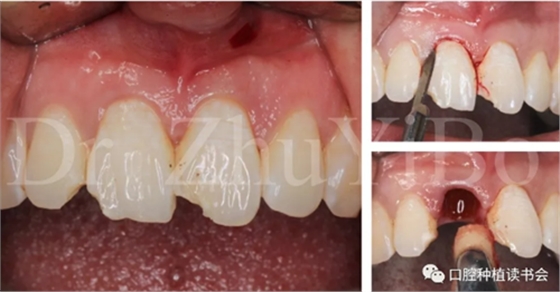

治療計(jì)劃:微創(chuàng)拔除右上中切牙,拔牙后即刻種植+即刻修復(fù);同期采用雙區(qū)植骨技術(shù)。

4.2.1微創(chuàng)拔出牙齒,挺出根尖(圖9)

圖9 斷裂牙根需用微創(chuàng)器械拔除

4.2.2 拔牙窩沖洗,定點(diǎn),備洞(圖10)。

圖10 種植窩洞相對于天然牙長軸偏向腭側(cè)